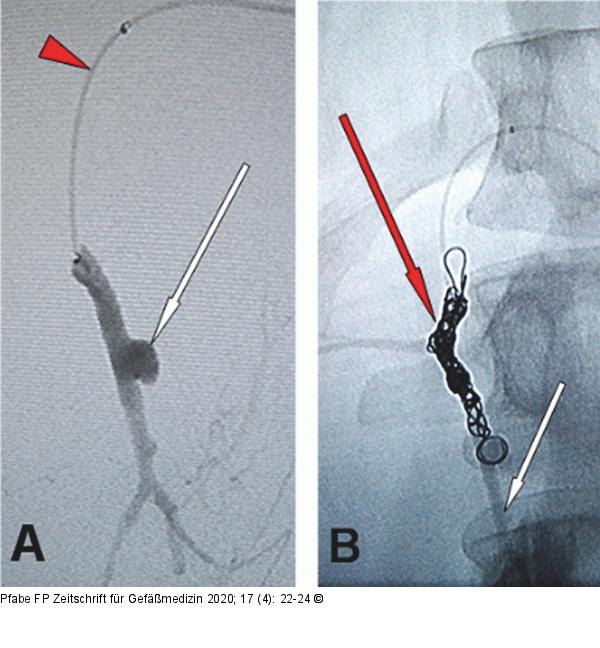

Abbildung 4: A. gastroduodenalis Selektive Darstellung der A. gastroduodenalis nach Sondierung mit einem Mikrokatheter. (A): Darstellung in DSA-Technik nach selektiver Sondierung mit einem Mikrokatheter (roter Pfeil), Visualisierung des umschriebenen Paravasats (weißer Pfeil); (B): A. gastroduodenalis nach Coil-Embolisation (roter Pfeil) und nachweisbarer Kontrastierung distal des embolisierten Gefäßabschnittes unmittelbar nach Einbringen der Coils (weißer Pfeil). |

Selektive Darstellung der A. gastroduodenalis nach Sondierung mit einem Mikrokatheter. (A): Darstellung in DSA-Technik nach selektiver Sondierung mit einem Mikrokatheter (roter Pfeil), Visualisierung des umschriebenen Paravasats (weißer Pfeil); (B): A. gastroduodenalis nach Coil-Embolisation (roter Pfeil) und nachweisbarer Kontrastierung distal des embolisierten Gefäßabschnittes unmittelbar nach Einbringen der Coils (weißer Pfeil). |